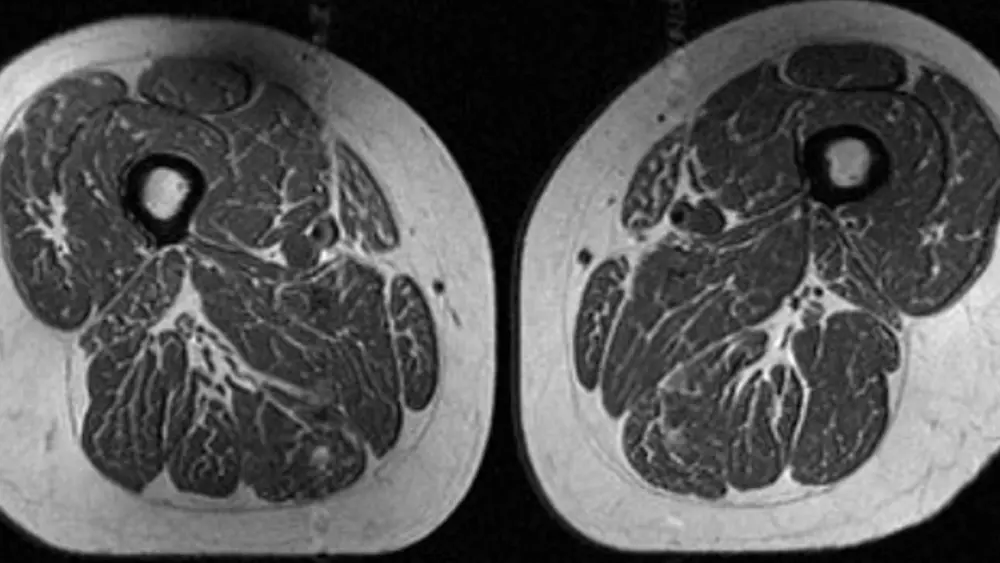

Ultraprocessed foods are turning human thighs into well-marbled steaks

Ultraprocessed food intake was linked to more thigh muscle fat on MRI in a new study. Learn how diet may affect muscle quality and knee health.